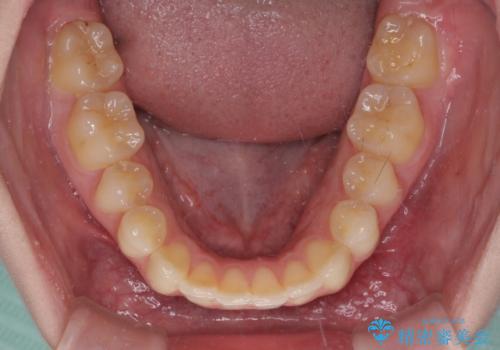

下顎の骨格的なズレが大きかったため、上下歯列のバランスが取れるか心配でしたが、上下ともに左右対称に近い歯列で治療を終えることができました。